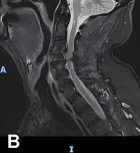

Diagnostic Testing. One day after admission, an initial brain MRI revealed a necrotic, contrast-enhancing lesion in the right occipital lobe with surrounding vasogenic edema, along with smaller enhancing nodules near the right lateral ventricle and in the left cerebral hemisphere (Figure 1A). Four days following admission, cervical and thoracic spine MRI demonstrated punctate enhancing foci within the proximal spinal cord and pons (Figure 1B), making findings initially suspicious for metastatic disease.

Figure 1A-B. (A) Initial brain MRI shows a necrotic, enhancing lesion with surrounding edema in the right occipital lobe. Several small enhancing nodules are seen near the right occipital and temporal horns in the left hemisphere. (B) Sagittal view of thoracic and cervical MRI with prominent focus at the level of T4 shows punctate enhancing foci scattered within the proximal spinal cord and pons, findings suspicious for metastatic disease.